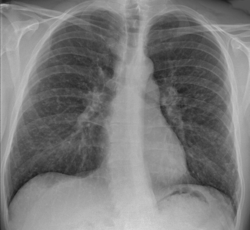

Əlamətləri: Gənc və orta yaş qrupunda daha çox görünən, əsasən də 40 yaşdan aşağı və ən çox qadınlarda rast gəlinən bu xəstəlikdə diaqnoz qoymaq üçün heç bir simptom və əlamət yoxdur, şikayətlər xəstəliyin tutduğu orqana xas olur. Bir çox xəstədə heç bir simptom görünmür və diaqnoz təsadüfən çəkilən ağciyərin rentgenoqramması ilə qoyulur. Xəstələrin təxminən 25–30%-də halsızlıq, iştahasızlıq, yüksək temperatur kimi ümumi əlamətlər mövcuddur. Bəzi xəstələrdə temperatur, oynaq ağrıları, yorğunluq, halsızlıq, ayaqların ön tərəfində sərt ağrılı qırmızımtıl-bənövşəyi rəngli düyünlərin meydana çıxması ilə xəstəlik kəskin bir şəkildə başlaya bilər. Ağciyər tutulubsa öskürək, təngnəfəslik, sinə ağrısı, xırıltılı tənəffüs, nadir hallarda qanhayxırma kimi simptomlar olur. Bəzən müayinə zamanı boyun, qoltuqaltı və ya başqa bir sahədə böyümüş limfa vəziləri müəyyən olunur. Xəstəlik ağciyərdən kənar daha çox gözlərdə görünür və gözdə olması qızartı, bulanıq görmə, işıqdan narahat olma kimi əlamətlərlə özünü göstərir. Dərini tutubsa, dəri üzərində dəyişik xarakterdə qabarıq və zədələnmiş nahiyələr görünür. Bəzi hallarda beyin tutula bilir və baş ağrısı, baş gicəllənməsi, görmənin zəifləməsi meydana çıxır. Sarkoidoz xəstələrində böyrək daşının əmələ gəlmə riski daha yüksəkdir və belə xəstələrdə sidik aktının pozulması, bel ağrıları daha çox yaranır. Uşaqlarda isə dəri və limfa vəzilərini daha çox tutur, yaş azaldıqca xəstəliyin yayılması artır və xəstəliyin proqnozu daha da pisləşir. Belə ki, xəstəlik uzun müddət və ağır formada davam edərsə, ağciyərlərin fibrozuna və tənəffüs funksiyasının azalmasına gətirib çıxara bilər. Diaqnostikasinda əsas amil rentgenoqramda hər iki və bir ağciyər qapısı limfa düyününün adenopatiyasi şübhələnməyə əsas verir. Qan analizlərində eozinofiliya 5%dan çox olur. Temperatur 39–40 dərəcəyə qədər yüksəlir.